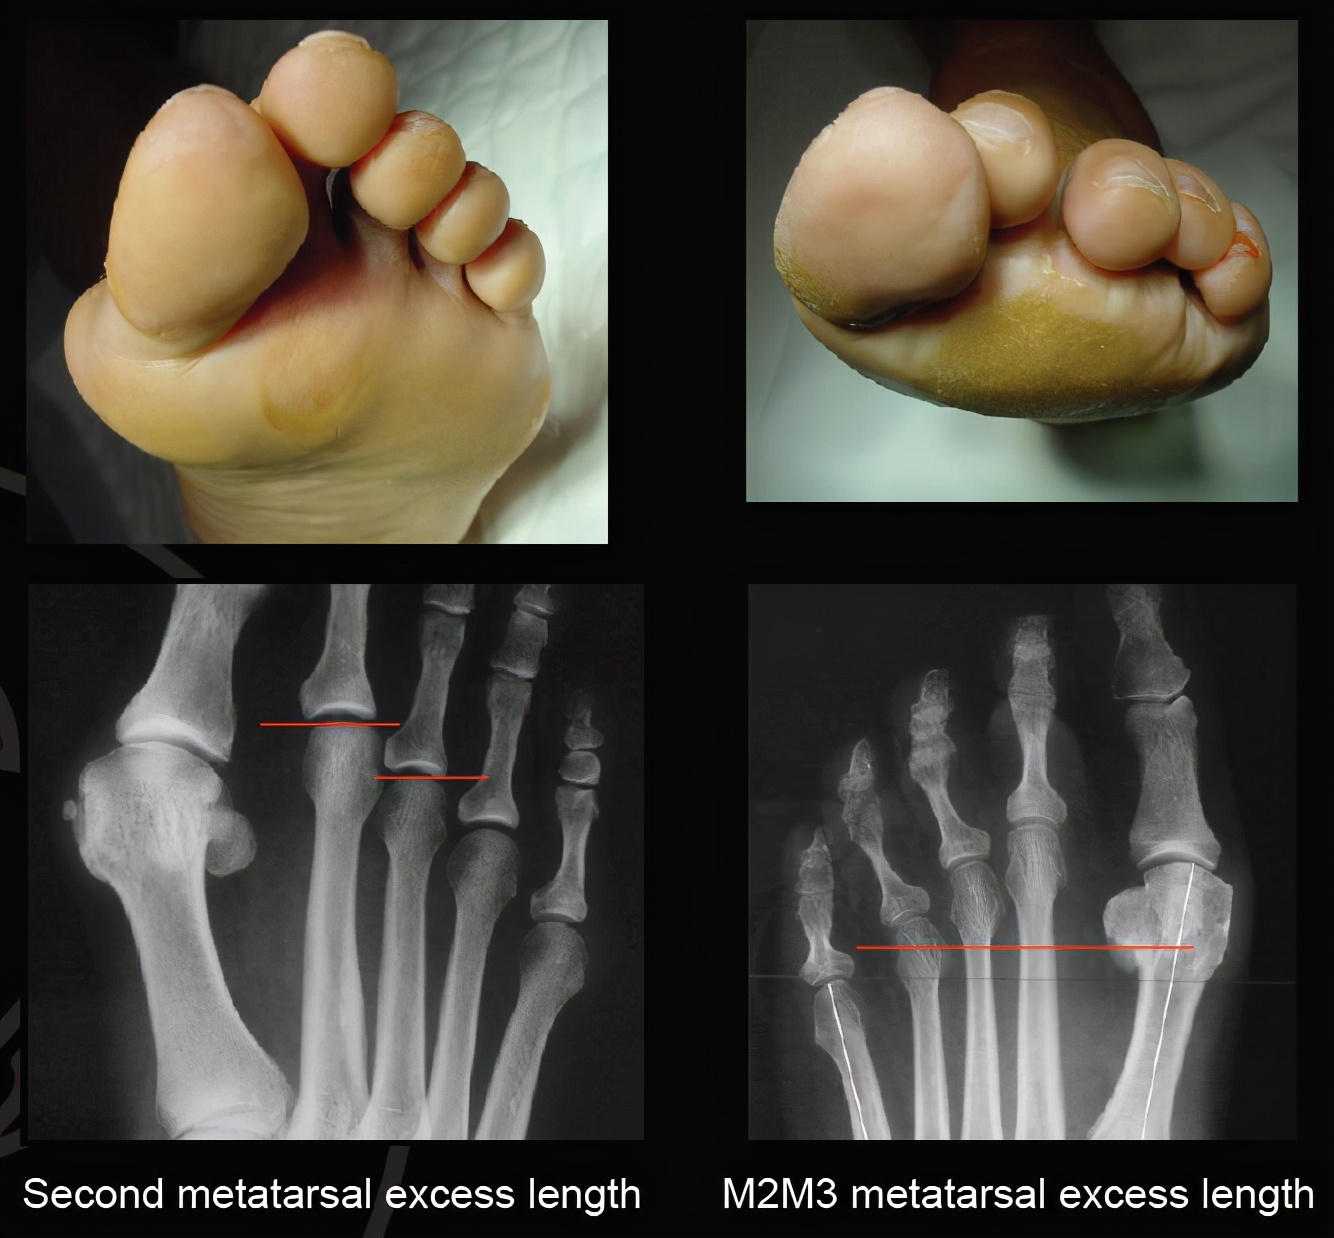

今天因为比较忙,我就不写太多,少写一些内容。大家先看看这个图片:

前足茧子与跖骨的关系

导致前足长茧子主要有几个因素,比方说拇外翻导致前足足横弓塌陷;比方说跖骨长短不协调,上图这个案例就是典型的跖骨长短不协调导致的第二三跖趾关节下方长茧子。

前足的负重主要有第一跖趾关节负重,然后合并前足的足横弓这个特点,就能负责弹跳及日常负重等情况。我们可以看到第一跖骨明显比其余跖骨要粗大,而且第一跖骨下方还有起缓冲作用的籽骨。当第一跖骨过短的时候,或者因为拇外翻导致第一跖骨上抬的时候,本来应该由第一跖骨承受的重力转移到了第二跖趾关节,尤其是图一那种第二跖骨绝对长度较长的朋友们,其第二跖骨会抢着来承受重力,而第二跖趾关节本来设置的时候并不能承受如此重力,第二跖趾关节为了更好承受重力,就只有增加受力面积,这就是第二跖趾关节下方长茧子的原因,讲到这里,你有明白了吗?